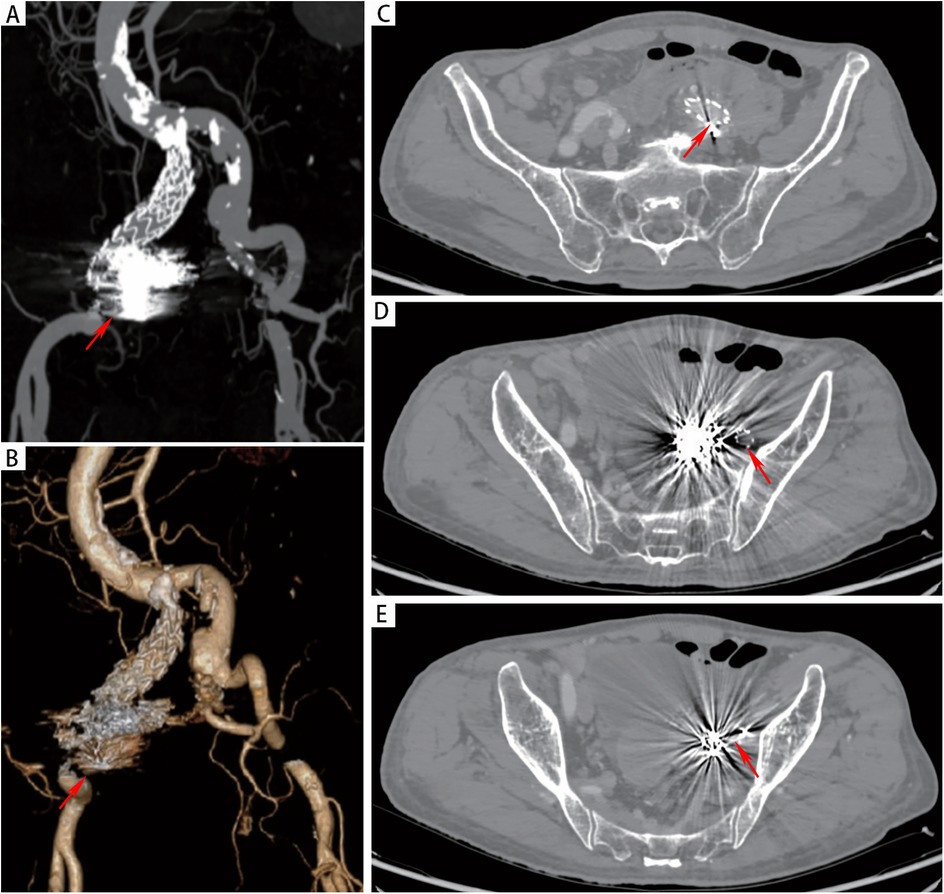

An 82-year-old male presented to the emergency department with a half-month history of intermittent hematochezia, with an estimated blood loss of 100–200 ml per episode. He also reported generalized weakness, dizziness, lower abdominal pain, and occasional passage of blood clots. The patient denied abdominal distension, diarrhea, fever, or bowel obstruction, and reported no significant recent weight change. His medical history included coronary artery disease, smoking, and COPD. There was no prior surgical or trauma history. Physical examination revealed a pulsatile mass in the left lower abdomen without significant tenderness. The extremities were cool and clammy, with poor peripheral perfusion. Vital signs on admission were: temperature 36.3°C, heart rate 122 beats/min, respiratory rate 23 breaths/min and blood pressure 115/78 mmHg. Laboratory investigations revealed anemia (hemoglobin:75 g/L; reference range: 114–154 g/L), hypoalbuminemia (albumin:25.8 g/d; reference range: 40–55 g/L), renal insufficiency (serum creatinine:1.34 mg/dl; reference range: 0.6–1.2 mg/dl) and acute heart failure (B-type natriuretic peptide: 1,125 ng/L; reference range < 226 ng/L). Other parameters were within normal limits. Computed tomographic angiography (CTA) demonstrated a 32 × 27 mm right common iliac artery aneurysm and a 20 × 27 mm left common iliac artery aneurysm. A 66 × 51 mm aneurysm was identified in the left internal iliac artery with extensive intramural thrombus (Figure 1A). Furthermore, the rectal wall showed irregular thickening with focal discontinuity along the left upper wall (Figures 1B,C), suggestive of a fistula between the left internal iliac artery aneurysm and the rectum. Emergency colonoscopy revealed an ulcer with active bleeding at 13 cm from the anal verge (Figures 1D,E); a biopsy of the surrounding tissue was obtained. The patient was diagnosed with: (1) left internal iliac artery–rectal fistula; (2) hemorrhagic shock; (3) hypoalbuminemia; (4) renal insufficiency; (5) coronary artery disease; (6) acute heart failure and (7) COPD.

Figure 1

(A) CTA revealed a left internal iliac aneurysm (red arrow) and bilateral common iliac artery aneurysms (green arrow). (B) The red arrow indicated the left internal iliac artery aneurysm, with the rectum (green arrow) located below it. (C) CTA revealed that there was an unclear boundary between the left internal iliac artery aneurysm (red arrow) and the rectal wall (green pentagon). (D-E) Endoscopic evaluation revealed a raised, blood clot-adherent ulcer (arrows) on the rectal lateral wall.